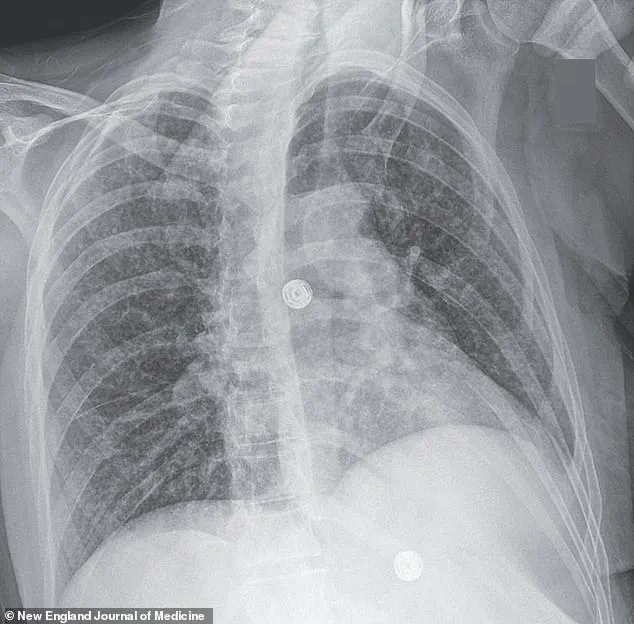

Doctors observed worsening oxygen levels and labored breathing, prompting a series of scans.

X-rays revealed small nodules in her lungs, a telltale sign of bacterial infection.

Further imaging uncovered lesions in her liver, lymph nodes, pancreas, and brain—indications that the infection had spread far beyond her respiratory system.

Consider the case of a woman whose medical scans revealed nodules in multiple organs, including her lungs, liver, pancreas, and brain.

These images, captured through advanced imaging techniques, illustrated the insidious nature of the disease.